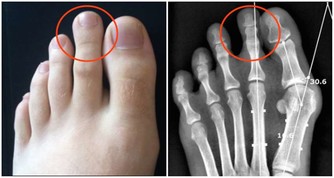

人就越長壽呢?研究發現,人腳部的筋越軟,人就越長壽。

把腳部的筋拉軟,不僅能夠變的強壯,延年益壽,而且還能夠改善人不好的脾氣,

腳部拉筋,簡單一招,最有效!

拉腳部的筋不能用常規的拉筋的方法,最好的方法是雙腳底底面相對互相對拍。